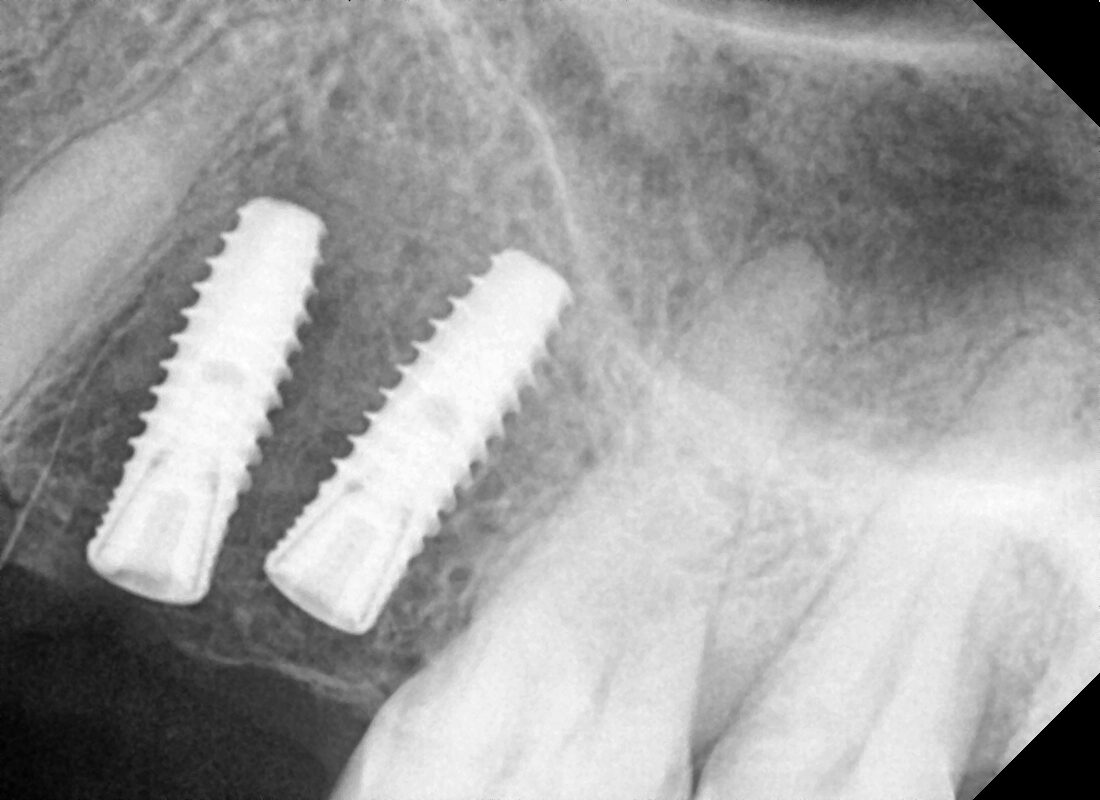

Prices are dynamic and starts from 12000 onwards… In this we have placed two Dentium implant which cost the patient 15000/implant Reply

Prices are dynamic and starts from 12000 onwards… In this we have placed two Dentium implant which cost the patient 15000/implant

dentium, osstem, pivot,